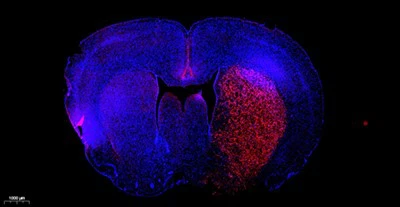

Hoechst 33258 का आणविक सूत्र C25H24N6O·3HCl है, आणविक भार 533.88 है, और CAS संख्या 23491-45-4 है। होचस्ट 33258 एक नीली फ्लोरोसेंट डाई है जो कोशिका झिल्ली में प्रवेश कर सकती है, और डबल-स्ट्रैंडेड डीएनए के साथ संयुक्त होने पर इसकी फ्लोरोसेंस काफी बढ़ जाती है। अधिकतम उत्तेजना तरंगदैर्ध्य 346 एनएम है, और अधिकतम उत्सर्जन तरंगदैर्घ्य 460 एनएम है। होचस्ट 33258 का उपयोग आमतौर पर एपोप्टोसिस का पता लगाने, परमाणु धुंधलापन, या नियमित डीएनए धुंधलापन के लिए किया जाता है। इसका उपयोग स्थिर कोशिकाओं और ऊतकों या गैर-स्थिर कोशिकाओं और ऊतकों के नाभिक को दागने के लिए किया जा सकता है। धुंधला होने के बाद, इसे प्रतिदीप्ति माइक्रोस्कोप द्वारा देखा जा सकता है या फ्लो साइटोमेट्री द्वारा पता लगाया जा सकता है। जब प्रतिदीप्ति सूक्ष्मदर्शी द्वारा देखा जाता है, तो यह पराबैंगनी प्रकाश, जो नीली प्रतिदीप्ति है, से उत्तेजित होता है।

बी। (वैकल्पिक चरण) यदि स्थिर कोशिकाओं या ऊतकों को इम्यूनोफ्लोरेसेंस स्टेनिंग से उपचारित करने की आवश्यकता है, तो संबंधित उपचार पहले किया जाना चाहिए, और फिर उपचार के बाद होचस्ट 33258 स्टेनिंग किया जाना चाहिए;